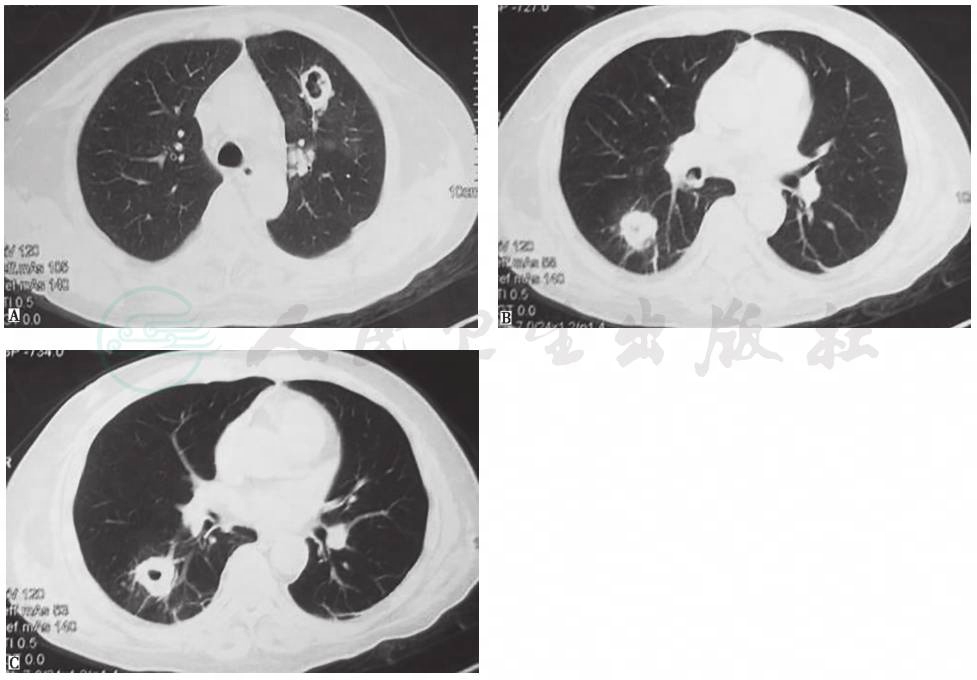

系列胸部影像学检查表现见图1~图5。

图1 X线胸片(2009-11-04)

X线胸片示左下叶斑片影,右上肺纹理增多

图2 X线胸片(2009-11-11)

X线胸片示左下叶斑片影较前明显吸收

图3 胸部CT表现(2009-11-09)

胸部CT示双肺散在小结节、斑片影,双侧少量胸腔积液

图5 胸部CT表现(2009-11-19)

胸部CT示双肺多发结节、空洞影

3.胸部影像学特点为病初见左下肺斑片影,莫西沙星治疗后肺部阴影吸收,停用后肺部阴影短期内再次增多。